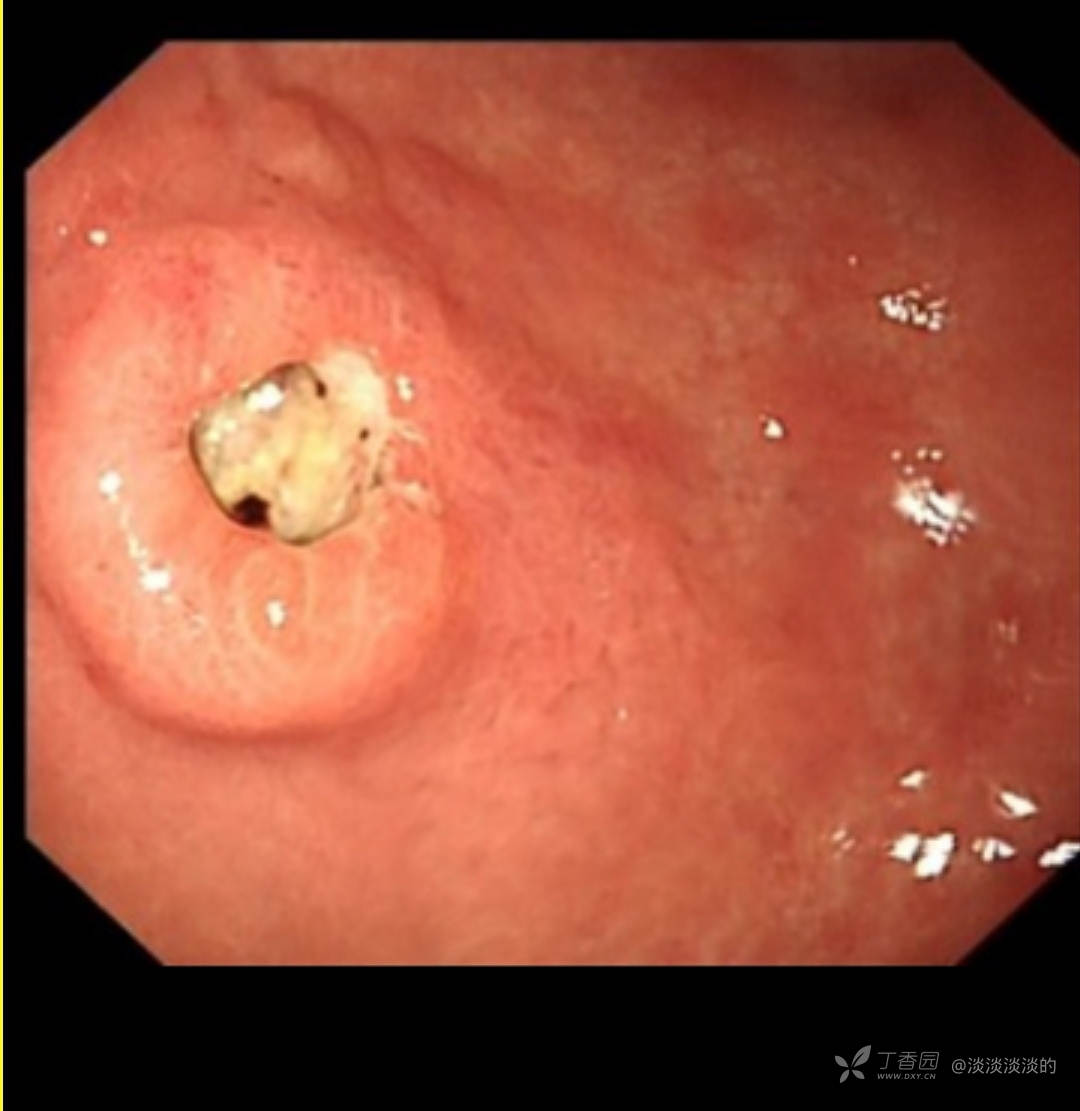

60岁女性,18年胃镜检查提示慢性胃炎,此次因上腹痛1月就诊,门诊检查发现胃窦前壁近胃角一病变,内镜,病理,增强CT如下,常规化验血检查没有明显异常,因病理良性,复查胃镜见最后1张,活检报告未出。